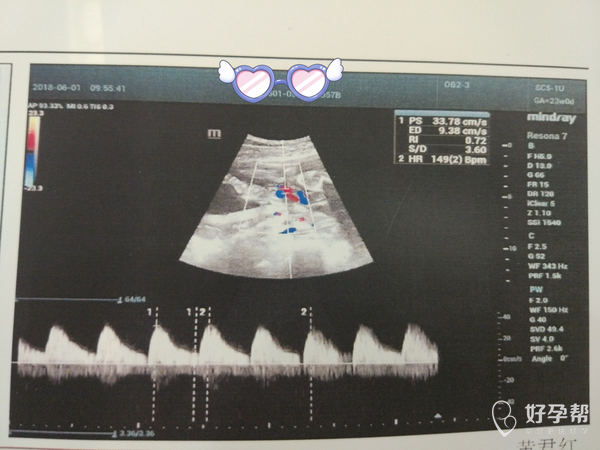

医生帮我看一下三维图

这个图片上的信息我看不懂,麻烦医生帮忙解答一下,谢谢

把B超书面报告发过来我看看

您好,需要看后面文字部分,传过来一下。

图片只是一个切面截图,不能反映综合情况。

你好,你发的这个图不清楚,我们没有看到中间的m号啊。